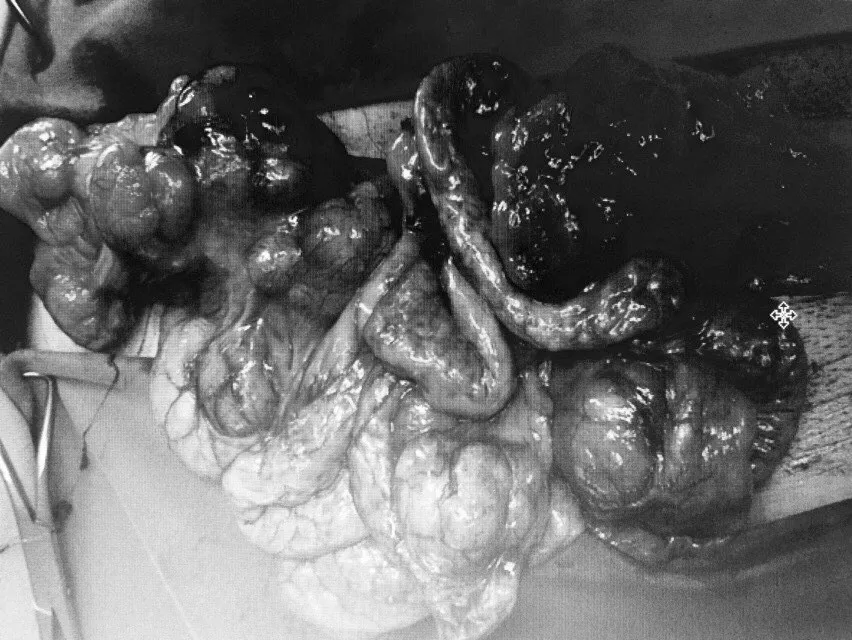

Các khối u được phẫu thuật lấy ra khỏi cơ thể bệnh nhân

Qua xét nghiệm và chụp chiếu cho thấy, bệnh nhân có những khối u xuất phát từ thân vị xâm lấn lách, kích thước lớn nhất 13x8cm, ngoài ra nằm rải rác khắp ổ bụng có rất nhiều u kích thước to nhỏ khác nhau, trong đó có một số khối u gây tắc ruột non, ổ bụng có dịch.

Kíp phẫu thuật đã cắt bỏ một phần dạ dày kèm lách, cắt nhiều đoạn ruột bị u xâm lấn nguy cơ gây tắc ruột tương lai, lấy tối đa u lử tiểu khung và những u rải rác trong ổ bụng.